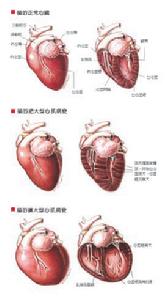

(三)收縮性或舒張性心衰 因心臟收縮功能障礙致收縮期排空能力減弱而引起的心衰為收縮性心衰。臨床特點是心腔擴大、收縮末期容積增大和射血分數降低。絕大多數心衰有收縮功能障礙。充血性心衰時舒張功能異常的重要性,近年來日益受到重視。它可與收縮功能障礙同時出現,亦可單獨存在。舒張性心衰是由於舒張期心室主動鬆弛的能力受損和心室的順應性降低以致心室在舒張期的充盈受損,心室壓力—容量曲線向左上方移位,因而心搏量降低,左室舒張末期壓增高而發生心衰,而代表收縮功能的射血分數正常。舒張性心衰的發生機制有:①左室鬆弛受損。特別如在心肌缺血時,心肌肌漿網攝取Ca2 的能力減弱,心肌細胞內游離Ca2 的水平降低緩慢,致主動鬆弛受損;②心肌肥厚和心肌僵硬度增加(伴有心肌纖維化),舒張期心肌擴張能力減弱(順應性降低)。單純舒張性心衰常見於有顯著心肌肥厚、心腔大小正常並心率增快者,如高血壓心臟病的向心性肥厚期;主動脈瓣狹窄;肥厚型心肌病和缺血性心肌病等。

三、心室重塑

初始的心肌損傷使心肌肥厚,繼之以心室擴大,這就是心室重塑的過程心室重塑包括所有心臟成分:心肌細胞肥厚;細胞外基質一膠原網的量和組成的變化和微血管密度的增加。原發性心肌損害和心臟負擔過重引起的室壁應力增加,可能是心室重塑的始動機制而各種生長因子起了重要作用,其中血管緊張素Ⅱ可能是一系列生化反應的核心。

從心肌肥厚如何發展成心室擴大的機制尚不清楚心肌纖維的拉長,膠原網支架的破壞所引起的心肌細胞滑行都可能參與了心室擴大的過程。肥厚心肌的收縮速度降;收縮時間延長;鬆弛延緩但肌纖維縮短能力和心室排空能力並不減弱,因此,如果心肌有適當的肥厚而足以克服室壁應力時心室功能仍得以維持,即為心衰的適應階段;當心肌肥厚不足以克服室壁應力時,即進人適應不良階段左室進行性擴大伴功能減退,最終發展至不可逆性心肌損害的終未階段。心室重塑是引起進行性心衰和死亡的主導原因。

三、心肌損害和心室重構(remodeling)原發性心肌損害和心臟負荷過重使室壁應力增加,導致心室反應性肥大和擴大,心肌細胞和細胞外基質-膠原網的組成均有變化,這就是心室重構的過程。肥厚的心肌收縮速度下降;收縮時間延長;鬆弛延緩,但肌纖維縮短能力和心室排空能力並不減弱。因此如果心肌有適當的肥厚而足以克服室壁應力時,心室功能仍得以維持,臨床上亦不產生充血性心衰的症狀。因而,心肌肥厚在初期可起有益的代償作用。肥厚心臟如何發展至進行性心室擴大和心衰,其中機制尚不十分明了,能量耗竭可能是主要因素之一。由於肥厚心肌處於能量飢餓狀態,心肌缺血,心肌細胞死亡,繼以纖維化,剩下的存活心肌負荷進一步加重,心肌進一步肥厚伴進行性纖維化,如此形成惡性循環。當心肌肥厚不足以克服室壁應力時,左室進行性擴大伴功能減退,最後發展至不可逆性心肌損害的終末階段。上述三者之間是互相關聯,互為因果的。血流動力學異常可激活神經內分泌,加重心肌損害;神經內分泌的持續激活可直接損害心肌和加劇血流動力學異常;而心肌損害、左室進行性擴大和衰竭的結果又導致血流動力學紊亂的加重和神經內分泌的激活。